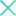

Clase 1 - Conceptos esenciales en fisiología y anatomía de la retina

Clase 3 - Más allá de la interopretación de OCT estructural papilar. Correlación histológica

Clase 15 - Depósitos y signos específicos en DMAE no neovascular

Clase 18 - Signos estructurales diferenciales entre neurodegeneración y exudación en DMAE